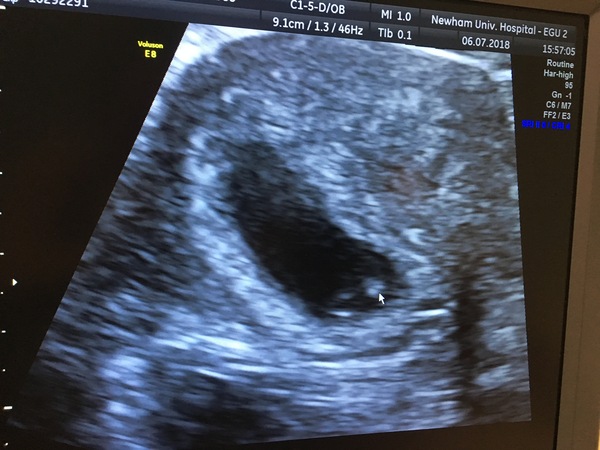

She found out a few weeks ago she was pregnant and went for a scan today.. this is what was found in her scan

They have referred her to the EPU Monday for another scan.. nothing much is being said but I wondered if you could help with any ideas as to if this is good news/ bad news or just too early? They have said there is a slight hemorrhage there also and to expect some spotting but as of yet there hasn't been any. She had a MMC in March this year also

Apparently she’s around 6 weeks but we reckon she could of ovulated later. What do you all think?

I'll attach the pics of her scan today

Thank you 🙂

@Alicejj8x it’s so difficult to say!! Obviously not a sonography expert... if your friend is likely to only be in week 5 then she more than likely wouldn’t have seen a little dot. They literally double in size from week to week at the start. Maybe that is why they have referred for another scan in a few days time to see if there is any growth? Fx everything goes smoothly for your friend xx

@Alicejj8x hopefully it's just a bit early for your friend. Being a few days out this early on makes a huge difference to what they can see. Did she wait til she had missed her period for a positive test and are her cycles regular as that could make a difference as to how far along she actually is. Did they do an internal scan or was it just abdominal?

I went for a scan at 7w and they put me back to 5+5. She had to do an internal scan to see things properly and even then she really had to take her time to see the embryos in the gestational sacs as they are just so tiny early on. My dates mean I would have had a positive test at something like 7dpo which would be v early but I suppose possible given it was a squinter & I have irregular cycles, could it be similar for your friend so she is actually just a week or so further behind than she thought & got a v early positive test?. Fx everything works out for your friend.

Yes so they are saying from her period she should be 6 weeks and they should be able to see more at 6 weeks apparently.

But her period was the 25th may so I reckon she's a few weeks behind me putting her at 4-5 weeks if not earlier possibly!

Yes they are sending her for a scan Monday so fingers crossed she'll be able to see more then

I know when I went last week they said it looked like I was 5ish weeks but we saw a heart beat so I'm thinking I'm possibly earlier on anyway

They did an internal scan but didn't say much apparently only that there was a bleed and to prepare for spotting but as of yet nothing.

I am thinking she's abit early and ovulated later I am hoping anyway for her.. ahh yes that's the same for me last week I had internal scan she said I looked 5ish weeks but didn't measure me and we saw a heart beat so I reckon I'm abit further on so I am hoping she's behind me abit and that's why they can't see anything.

Ahh ok yes that's very early isn't it I thnk the thing that worrying them is that there's no yolk sac atm just the gestational sac ..

Hopefully Monday will be able to tell her more now. Thank you xxx